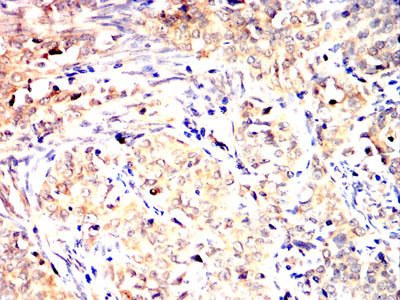

![TLT2 Mouse mAb[64327]](https://img1.dxycdn.com/p/s14/2025/0922/561/8212114244418699691.jpg)

Immunohistochemical analysis of paraffin-embedded human cervical cancer tissues using TLT2 mouse mAb with DAB staining.